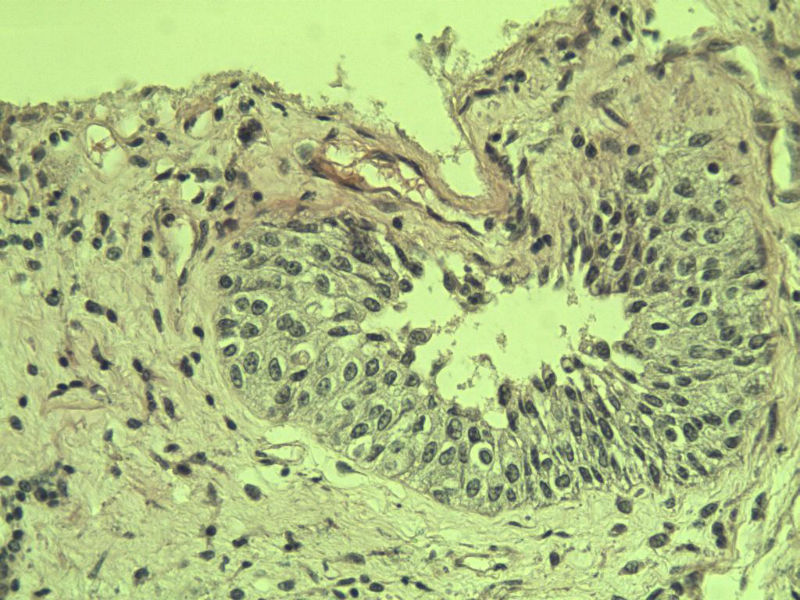

男 75岁 因排尿困难半年行前列腺切除术,体积 4 × 3 × 2.5 cm3,切面灰白,实性,质韧。请各位老师看看 有问题没? 谢谢了!

良性前列腺增生伴尿路上皮化生

前列腺增生症伴鳞化

前列腺增生伴尿路上皮鳞化及Brown巢形成,未见恶性。

前列腺增生,有腺瘤样结节形成。